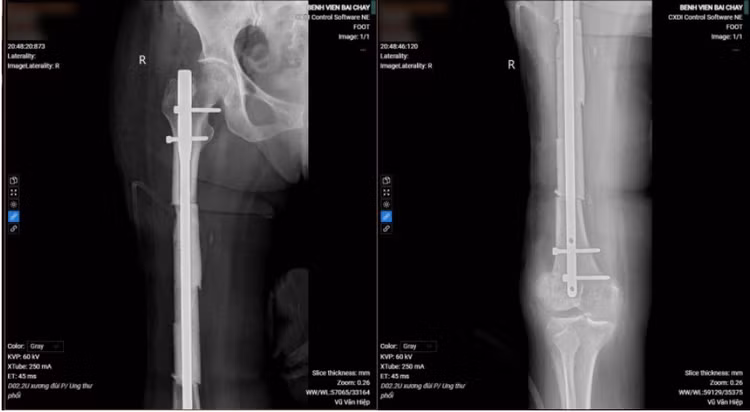

Tại đây, các bác sĩ đã khám, thực hiện các xét nghiệm chẩn đoán chuyên sâu để tìm ra căn nguyên gãy xương đùi. Kết quả chụp xquang gãy xương đùi phải, CTscanner toàn thân phát hiện khối u thùy trên phổi trái, hạch trung thất và vùng cổ trái, tổn thương thứ phát não, tiêu xương ngành trên xương mu bên phải. Bệnh nhân được sinh thiết khối u làm giải phẫu bệnh.

Dựa trên kết quả thăm khám lâm sàng, cận lâm sàng, các bác sĩ chẩn đoán bệnh lý ung thư phổi không tế bào nhỏ giai đoạn IV di căn não, tiêu xương, gãy xương đùi phải.

![]() |

| Hình ảnh khối u phổi của bệnh nhân - Ảnh BVCC |